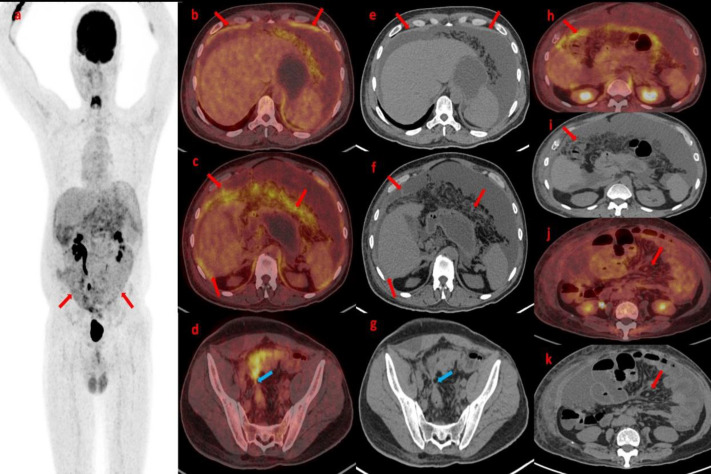

腹膜癌肿(PC)是癌细胞在腹膜中的扩散,是晚期胃肠道癌症和妇科癌症的一个重要问题。本病例系列包括 18F- 氟脱氧葡萄糖正电子发射断层扫描/CT(18F-FDG PET/CT)上 PC 的外观和模式。腹膜播散的主要来源是腹部或盆腔肿瘤的直接侵犯和远处肿瘤的转移扩散。准确的术前诊断和 PC 定量对确定适当的治疗方法起着至关重要的作用,尤其是在手术规划方面。术前评估采用了多种成像模式,如计算机断层扫描(CT)、磁共振成像(MRI)和 18F-FDG PET/CT。在这些方法中,18F-FDG PET/CT 显示了更好的解剖定位和病理结果性质的准确信息。本系列病例展示了四个病例,说明了 PC 在 FDG PET/CT 上的成像特点。FDG PET/CT 在诊断和评估 PC 方面发挥着重要作用,有助于 PC 的检测、分期和治疗计划。它在识别和描述病变以及在原发肿瘤位置不明的情况下检测原发肿瘤部位方面超越了传统的成像技术。此外,FDG PET/CT 还有助于评估治疗反应和监测疾病进展,为了解治疗效果和指导患者管理决策提供依据。

Peritoneal carcinomatosis (PC), the spread of cancer cells in the peritoneum, is a significant concern in advanced gastrointestinal and gynecological cancers. This case series includes findings on the appearance and pattern of PC on 18F-fluorodeoxyglucose positron emission tomography/CT (18F-FDG PET/CT). The primary sources of peritoneal dissemination are direct invasion from abdominal or pelvic tumors and metastatic spread from distant tumors. The accurate preoperative diagnosis and quantification of PC play a vital role in determining the appropriate treatment approach, with a particular emphasis on surgical planning. Several imaging modalities have been employed in preoperative evaluation, such as computed tomography (CT), magnetic resonance imaging (MRI), and 18F-FDG PET/CT. Among these modalities, 18F-FDG PET/CT has demonstrated improved anatomical localization and accurate information about the nature of pathological findings. The case series showcases four cases that illustrate the imaging characteristics of PC on FDG PET/CT. FDG PET/CT plays a vital role in diagnosing and assessing PC, aiding in its detection, staging, and treatment planning. It surpasses conventional imaging techniques in identifying and characterizing lesions and detecting the primary tumor site in cases where its location is unknown. Furthermore, FDG PET/CT additionally assists in evaluating treatment response and monitoring disease progression, providing insights into treatment effectiveness and guiding patient management decisions.